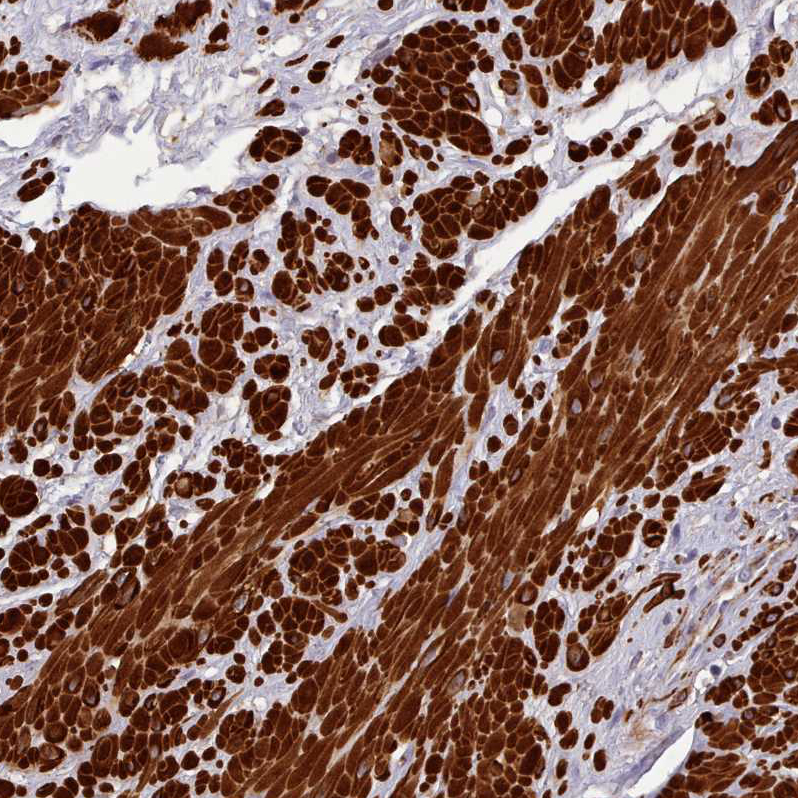

Immunohistochemical staining of human smooth muscle shows strong cytoplasmic positivity in smooth muscle cells.